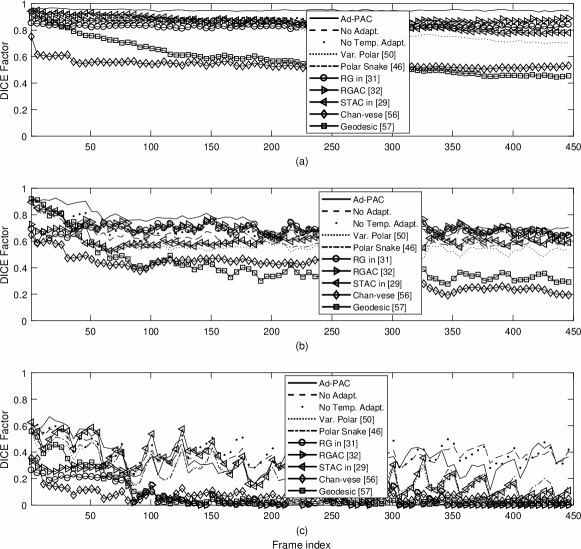

Ad-PAC performance was compared to expert manual segmentation, Ad-PAC without parameters adaptation, Ad-PAC without temporal adaptation, and two current state-of-the-art polar AC algorithms introduced in Section II [50, 51]. Additionally, it is also compared to region growing (RG) [31] and its combination with AC (RGAC) [32], Speckle tracking driven AC (STAC) [29], and two classic AC algorithms - Chan-Vese [56] and Geodesic [57]. For each of these algorithms, parameter optimization was accomplished using a small subset of videos with variable image quality. For each video, the first frame was manually segmented by an operator with subsequent frames segmented automatically.

Fig. 14 presents the DICE factors obtained from each algorithm, averaged across all 65 videos irrespective of IJV shape, intensity, speed of variation and quality. From this figure, it is clear that the proposed Ad-PAC algorithm outperforms all existing algorithms with its corresponding DICE factor greater than 0.64. Other algorithms perform significantly worse. In the following sub-sections, more detailed results are presented.

For this study, all videos were categorized, as good, average, and poor quality videos based on the blinded expert opinion. Fig. 16 illustrates the DICE results. In good quality ultrasound videos, as per Fig. 16-(a), the proposed Ad-PAC algorithm performs very close to the manual segmentation with a DICE factor consistently above 0.95. The minimum value of DICE factors for the other algorithms range from 0.91 down to 0.37 for the Geodesic algorithm [57].

In average quality videos, as shown in Fig. 16-(b), the performance of Ad-PAC algorithm drops as low as 0.65, however, it still outperforms the other AC algorithms. Poor quality videos (Fig. 16-(c)) demonstrate the minimum DICE factor as being 0.55, still above other algorithms.